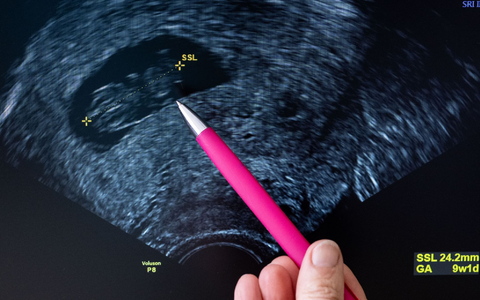

In Paragraf 218 des Strafgesetzbuches steht quasi ein Kompromiss: Eine Abtreibung ist in Deutschland grundsätzlich rechtswidrig, weil laut Grundgesetz das ungeborene Leben geschützt werden muss. Sie ist aber nicht strafbar, wenn sie innerhalb der ersten zwölf Wochen stattfindet und die Frau sich zuvor hat beraten lassen. Ohne Strafe bleibt ein Abbruch auch, wenn medizinische Gründe vorliegen oder wenn er wegen einer Vergewaltigung vorgenommen wird.

Laut Statistischem Bundesamt gab es in Deutschland im Jahr 2023 rund 106.000 gemeldete Schwangerschaftsabbrüche - rund 2,2 Prozent mehr als im Vorjahr. Oft sind junge Frauen betroffen, die meisten im Alter zwischen 18 und 34 Jahre. 96 Prozent der Abtreibungen wurden nach der Beratungsregelung vorgenommen. Medizinische Gründe und Sexualdelikte waren nur in vier Prozent der Fälle Grund für den Abbruch.